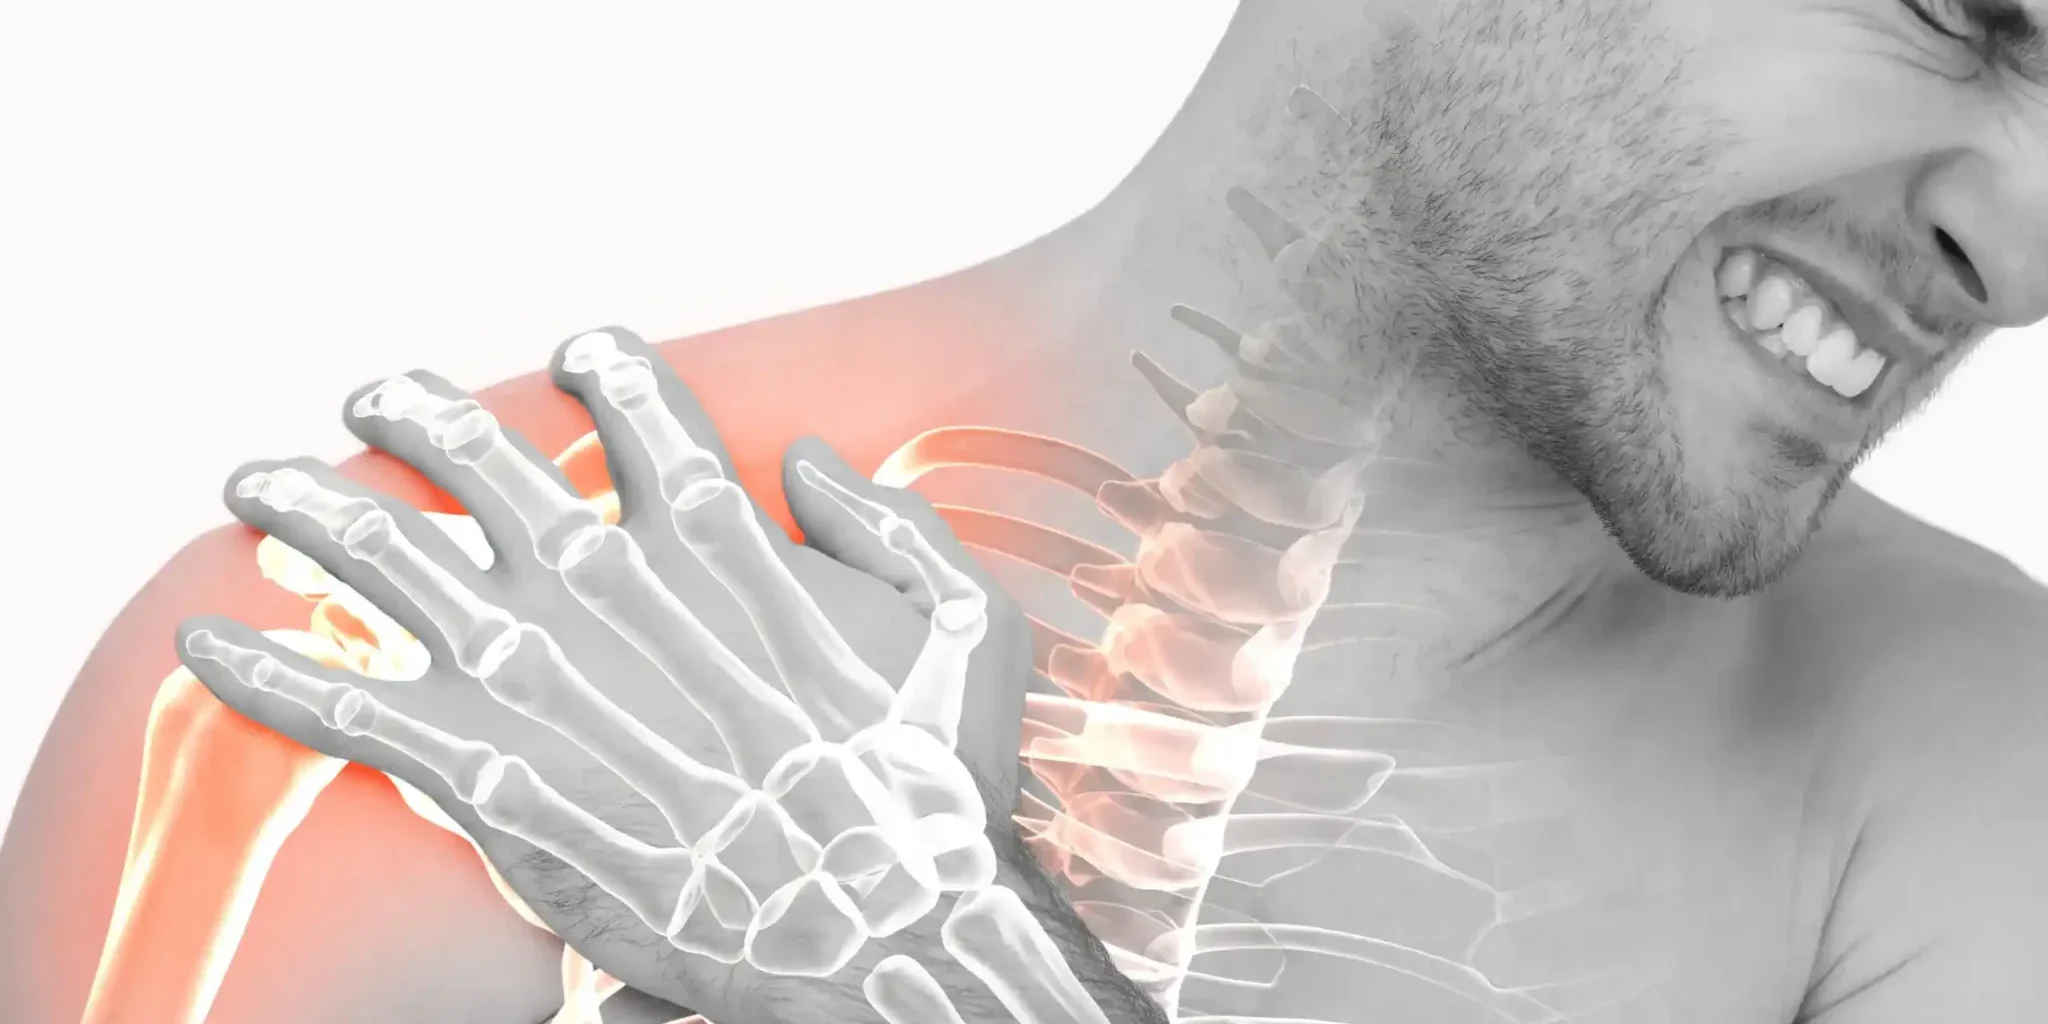

A pinched nerve occurs when surrounding tissues, such as muscles, tendons, bones, or cartilage, apply too much pressure to a nerve. This intense pressure disrupts the function of the nerve, causing pain, numbness, tingling, or weakness. Managing pinched nerve Woodstock requires proper management of the symptoms.

A pinched nerve can occur in various parts of your body. For example, the pressure on a nerve root due to a herniated disk in your lower spine can cause pain that radiates down the back of your leg. Likewise, you may experience pain and numbness in your hand and fingers (carpal tunnel syndrome) due to a pinched nerve in your wrist.

A pinched nerve occurs when the tissues surrounding a nerve apply too much pressure (compression) to it. In some cases, this tissue might be cartilage or bone, such as in the case of a herniated spinal disc that compresses the nerve root. In other cases, tendons or muscle may cause the condition.